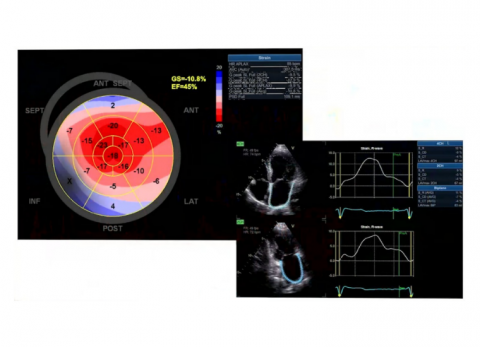

prof. dr hab. n. med. Jarosław KasprzakDane kliniczne:Pacjent z niewydolnością serca i przewlekłym zespołem wieńcowymRozpoznanie główne:Amyloidoza transtyretynowaNiewydolność serca z zachow...